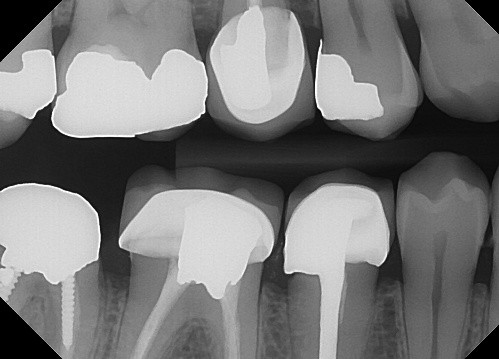

3. (Select ONE OR MORE correct answers)

The radiograph shows evidence of calculus on